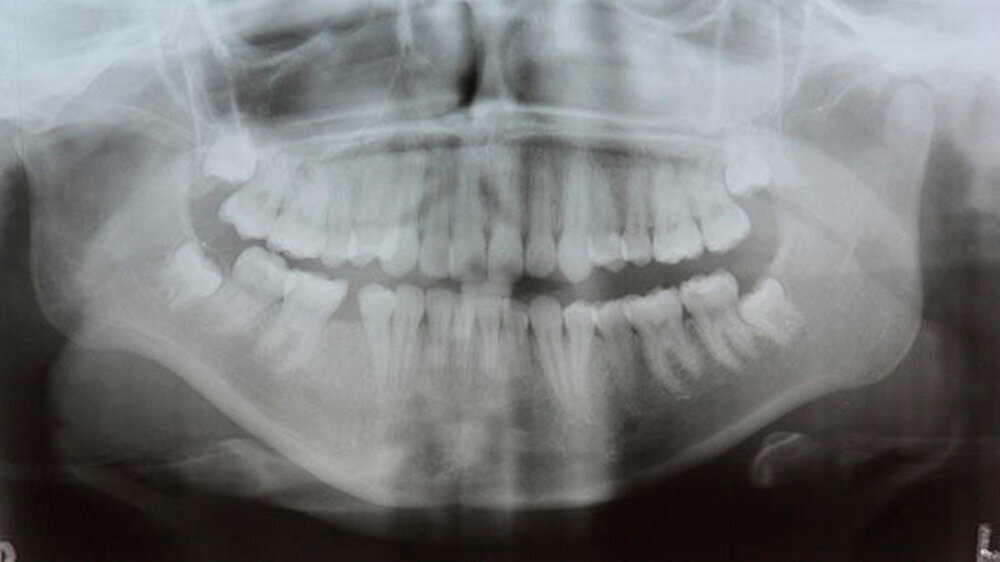

Die Patientin war gerade über 20 Jahre alt, als die Krankheit schleichend begann: Zunächst fiel der jungen Frau auf, dass der Kontakt zwischen den oberen und den unteren Schneidezähnen immer mehr verloren ging. Mit der Zeit wurde die Lücke immer größer, was im weiteren Verlauf ein Abbeißen unmöglich machte. Zudem bemerkte sie, dass ihr Kinn immer fliehender wurde, also immer weiter zurückfiel.

Daraufhin wurden eine kieferorthopädische Behandlung mit einer festsitzenden Spange und nacheinander zwei Operationen zur Umstellung des Ober- und Unterkiefers durchgeführt. Diese ersten Operationen konnten jedoch die weiter zunehmende Abweichung des Unterkiefers nach hinten und damit auch den offenen Biss nicht stoppen.

Diagnose: Resorption der Kiefergelenkfortsätze

Das Bonner MKG-Chirurgenteam um Prof. Dr. Dr. Rudolf Reich diagnostizierte eine zunehmende Einschmelzung (Resorption) der Kiefergelenkfortsätze, wodurch die gesamte Abstützung des Unterkiefers am Schädel verloren gegangen war.